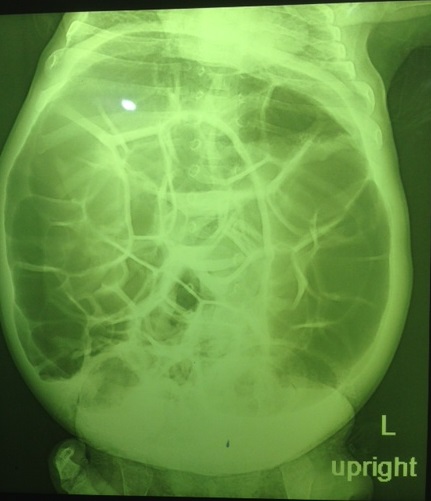

نوزاد پسر یک روزه فرزند اول خانواده با دیستانسون شکمی و استفراغ صفراوی به اورژانس آورده شده است. مکونیوم دفع کرده و در معاینه تون و رفلکس کاهش یافته است و ایکتریک می باشد. کدامیک از تشخیص های زیر مطرح نیست؟